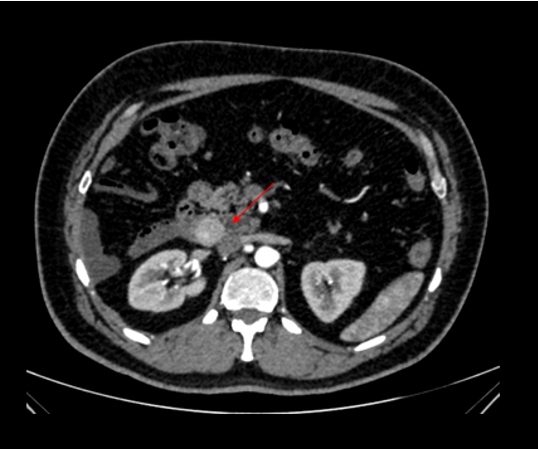

• A large altered signal intensity soft tissue lesion arising from the diaphysis of mid shaft region of humerus in posterior aspect with shallow surface cortical erosions, and spiculated periosteal reaction.

• The lesion demonstrates T2/STIR heterogeneous hyperintense signal and T1 hypointense signal with few cystic spaces. Multiple flow voids noted within lesion ( *). Mild intramedullary edema however no intramedullary extension.

• Broad-based cortically attached tumor with a partially mineralized soft tissue mass

• Extrinsic erosion of thickened underlying diaphyseal cortex with a surface-base crater

• Perpendicular or spiculated periosteal reaction

• Intramedullary extension is rare